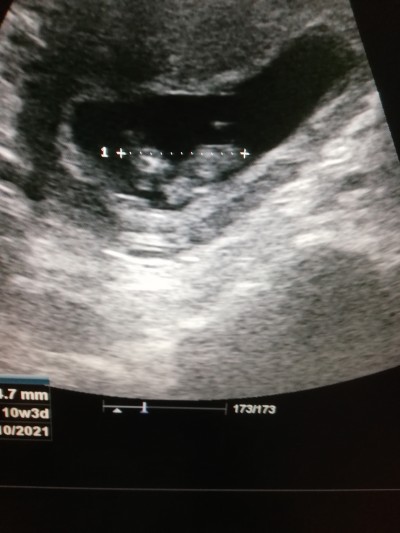

Doktora gıttım 11 haftalık olmuş dedi tarama testi yaptır haftaya dedi ultrasyonda belli kafasi falan cınsıyetı ne olabilir kızlar icinize ne doguyor

Gebelik haftası 10+4

Ultrasyonda 10hafta 3gun gorunuyo canm